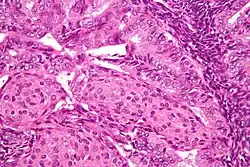

The histopathology of endometrial cancers is highly diverse. The most common finding is a well-differentiated endometrioid adenocarcinoma,[50] which is composed of numerous, small, crowded glands with varying degrees of nuclear atypia, mitotic activity, and stratification. This often appears on a background of endometrial hyperplasia. Frank adenocarcinoma may be distinguished from atypical hyperplasia by the finding of clear stromal invasion, or "back-to-back" glands, which represent nondestructive replacement of the endometrial stroma by the cancer. With progression of the disease, the myometrium is infiltrated.[61]

Grade 1: ≤5% solid non-glandular, non-squamous growth.[62] -

Grade 2: >5% and ≤50% solid non-glandular, non-squamous growth.[62] -

Grade 3: >50% solid non-glandular, non-squamous growth.[62] -

Nuclear grade 1: Oval, mildly enlarged nucleus with evenly distributed chromatin.[63] -

Nuclear grade 2: Intermediate features.[63] -

Nuclear grade 3: Markedly enlarged and pleomorphic nuclei, with coarse chromatin and distinct nucleoli.[63] -

Squamous growth seen as necrotic “ghost cells” of keratinocytes at right in image, leaving pink keratin.